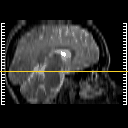

Click on sagittal image to select slice. Click on thin tickmark to change timepoint, or thick tickmark for overlay.